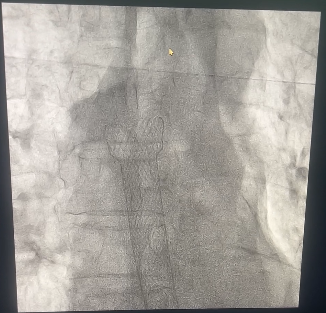

病情就是冲锋号。乔林邦主任迅速反应,立即启动绿色通道全力抢救,待患者病情稍稳,乔林邦主任迅速联合放射介入科主治医生吴华、秦小哲等组成攻坚团队,精心筹备并成功实施 “C 臂透视下食管内支架植入术”。

手术中,专家们凭借精湛技术和先进设备,精准定位并封堵了肺癌破入食管的瘘口,成功阻断了病情恶化路径。术后,患者恢复良好,目前已出院回家。